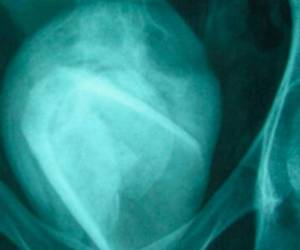

TEGUCIGALPA, HONDURAS.- La infección urinaria mejor conocida como mal de orín es una infección que se produce en el aparato urinario de hombres y mujeres -incluye la vejiga y uretra-.

A su vez, detalló que hay dos tipos de infección urinaria, entre ellas, la cistitis que se propaga en la vejiga, y la segunda, es la uretritis que se produce en la uretra.